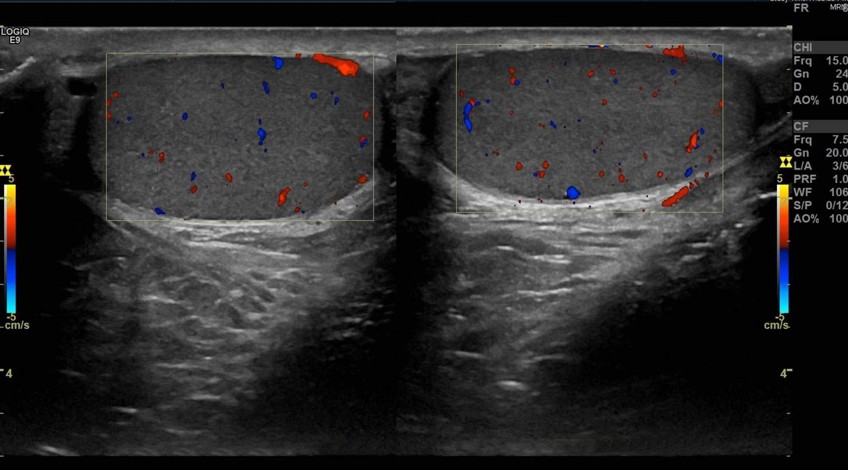

Ecotomografía Testicular

- ¿Qué es? Es un examen para estudiar la estructura de los testículos.